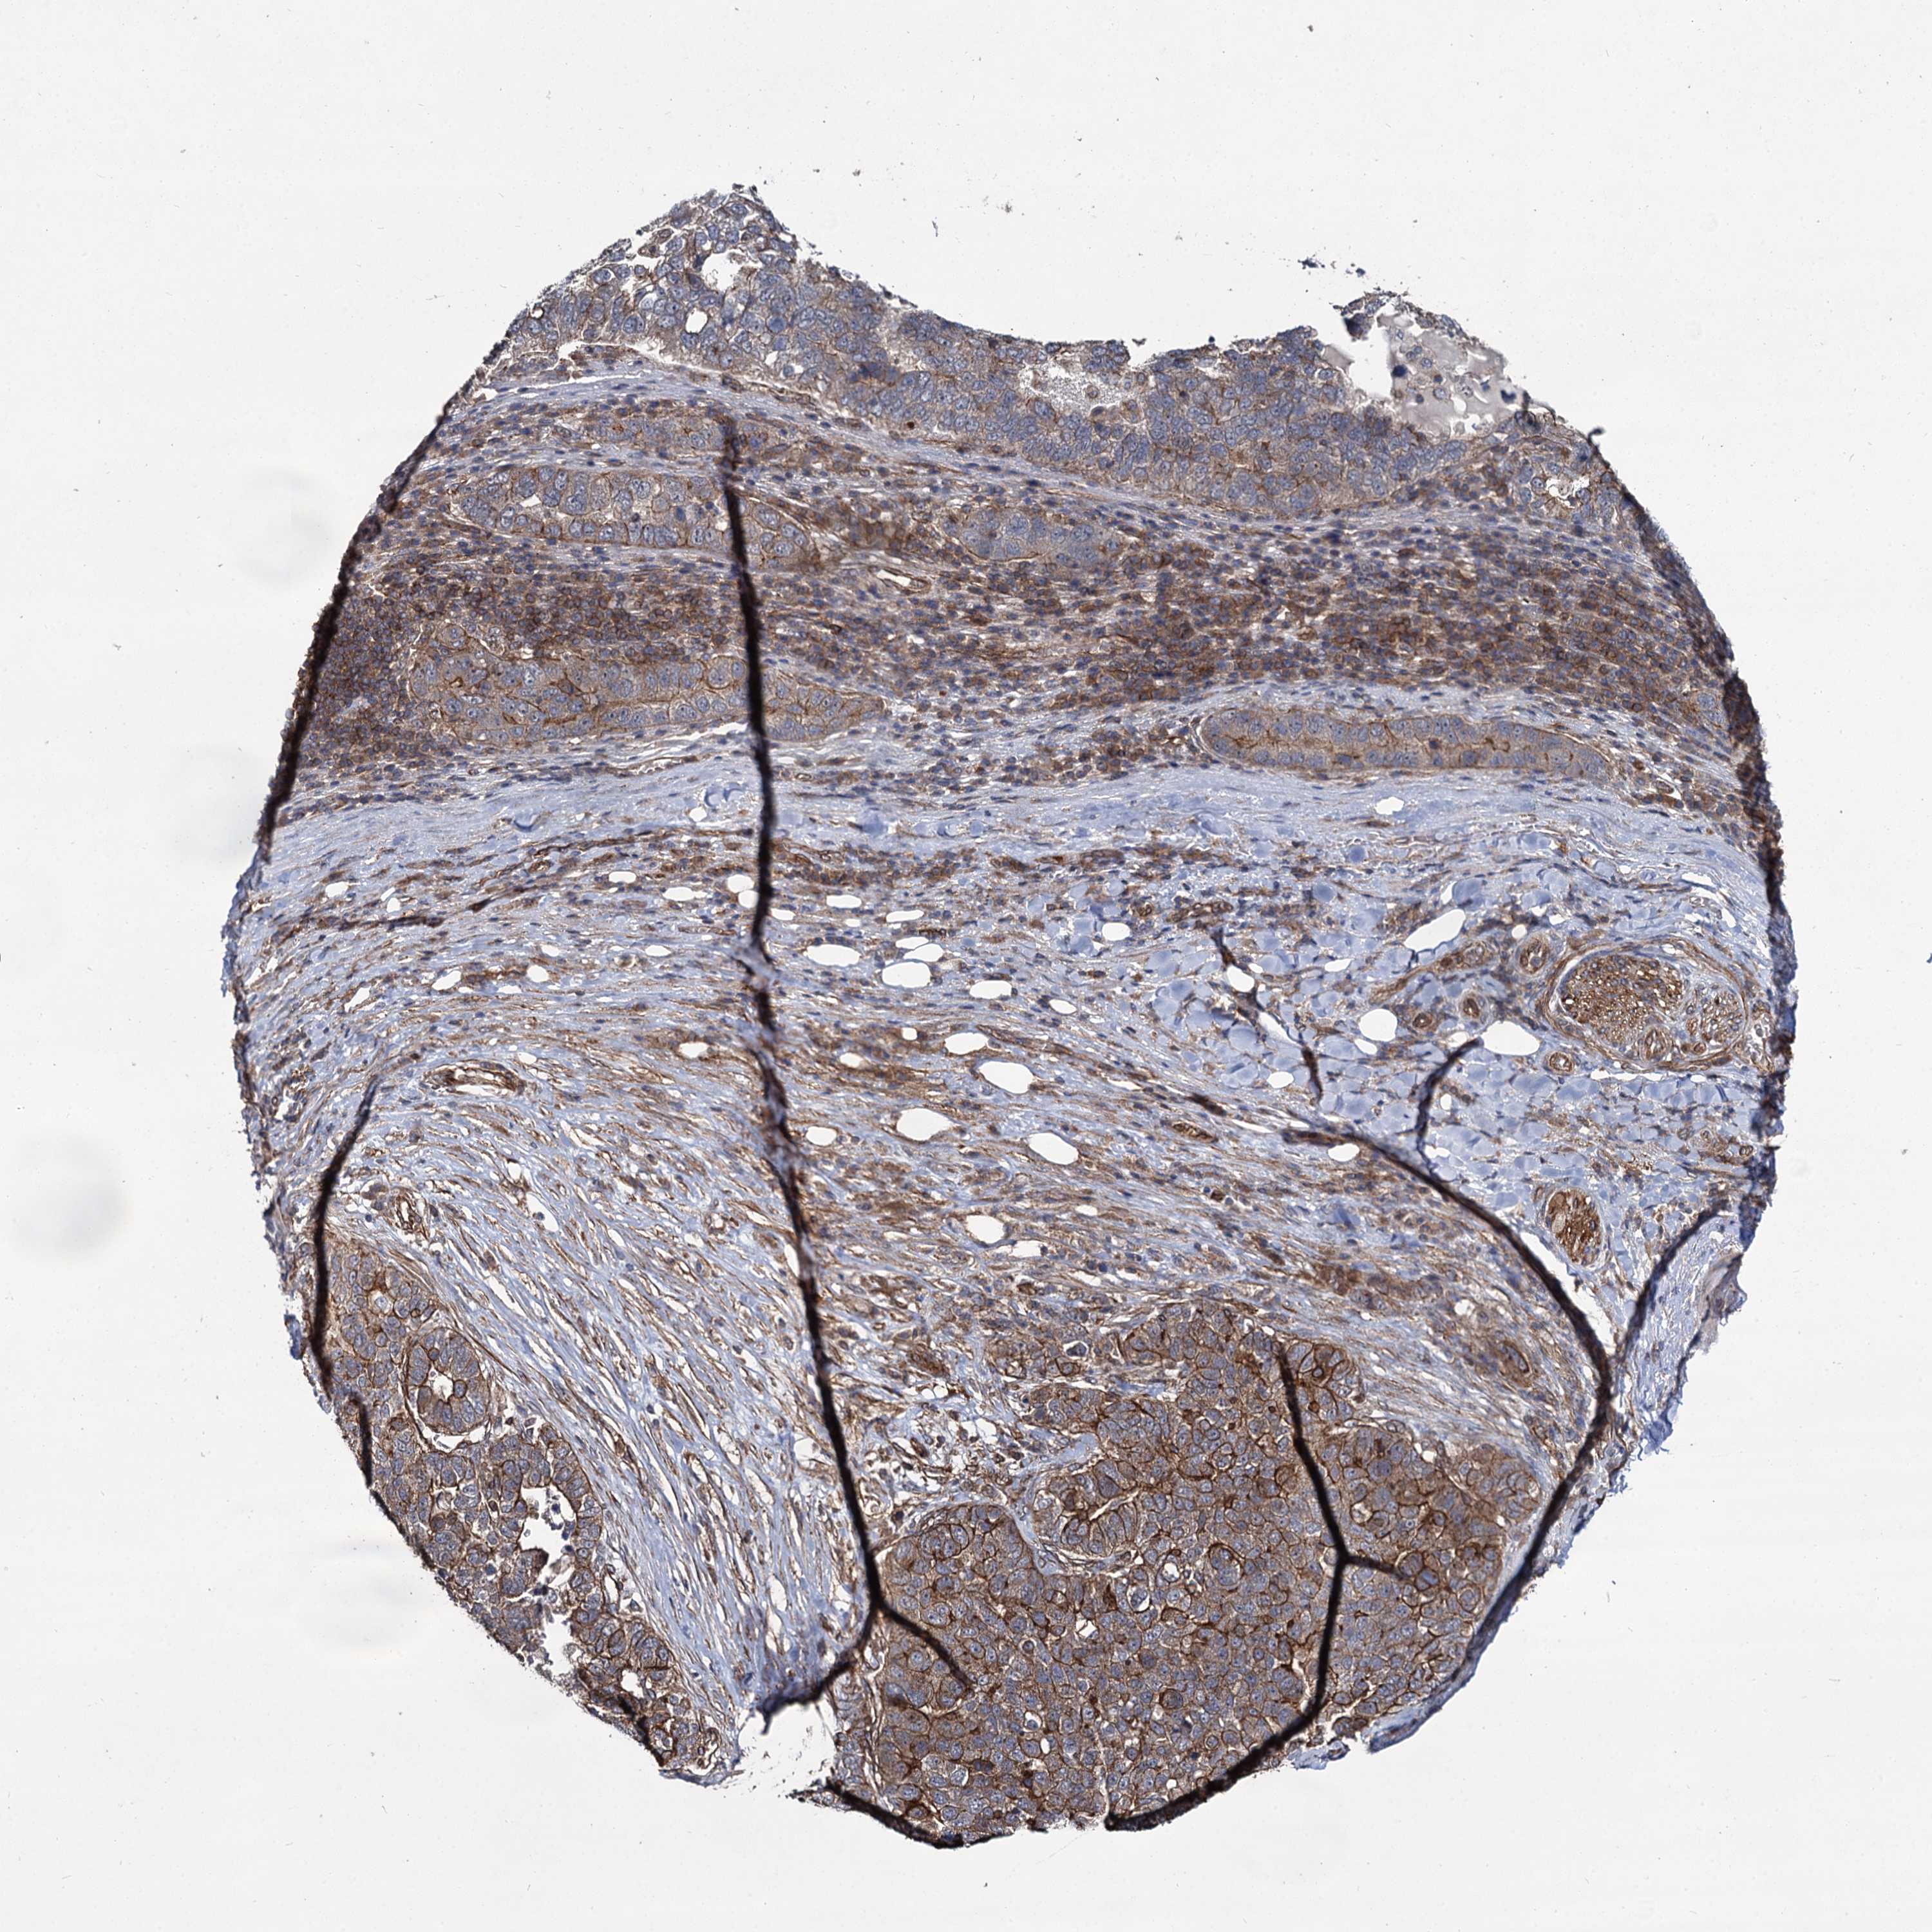

PANCREATIC CANCER - Protein expressioni

A mouse-over function shows sample information and annotation data. Click on an image to view it in a full screen mode. Samples can be filtered based on level of antibody staining by selecting one or several of the following categories: high, medium, low and not detected. The assay and annotation is described here.

Note that samples used for immunohistochemistry by the Human Protein Atlas do not correspond to samples in the TCGA dataset.

Antibody stainingi

Antibody staining in the annotated cell types in the current human tissue is reported as not detected, low, medium, or high, based on conventional immunohistochemistry profiling in selected tissues. This score is based on the combination of the staining intensity and fraction of stained cells.

Each image is clickable and will lead to virtual microscopy that enables deeper exploration of all samples and also displays staining intensity scores, fraction scores and subcellular localization as well as patient and tissue information for each sample.

Antibody HPA039807

Staining

High

Medium

Low

Not detected

Intensity

Strong

Moderate

Weak

Negative

Quantity

>75%

75%-25%

<25%

None

Location

Nuclear

Cytoplasmic/membranous

Cytoplasmic/membranous,nuclear

Adenocarcinoma, NOS